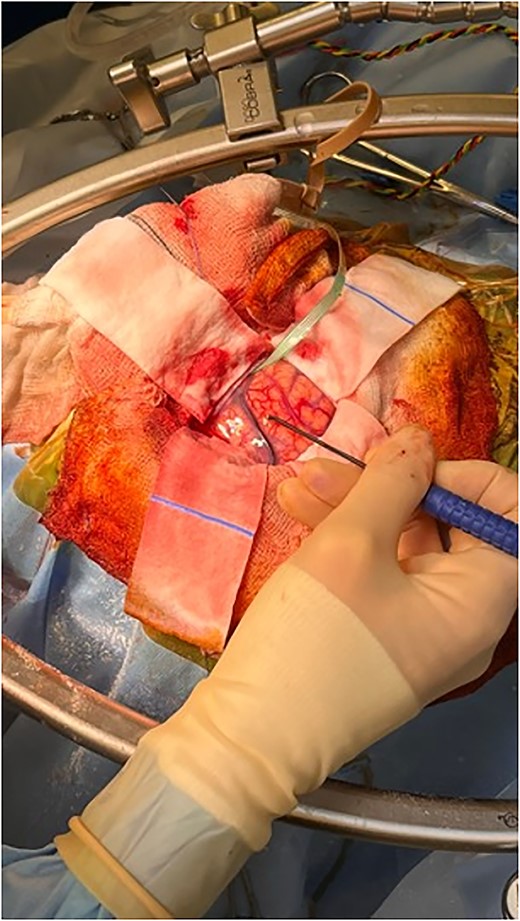

The patient was started on oral dexamethasone, resulting in the improvement of his headaches. The differential diagnosis based on imaging findings included an atypical meningioma, central neurocytoma, choroid plexus papilloma or carcinoma, ependymoma or an oligodendroglioma. He underwent a right parietal craniotomy with gross total resection of the lesion. Intraoperatively, use of the Vycor™ ViewSite Brain Access System (VBAS) was utilized, which allowed for optimized surgical site access, and reduced the risk of brain retractor injury to surrounding structures, namely the precentral gyrus. This was combined with intraoperative ultrasound (Fig. 3), which provided real time imaging and guided the extent of the resection. In addition, neuromonitoring and neuronavigation (Fig. 2) were incorporated to further reduce the risk of damage to surrounding structures. As part of the neuromonitoring, motor evoked potentials (MEPs) were performed to identify the precentral gyrus prior to insertion of the VBAS (Fig. 4), ensuring that any resection occurred posterior to the motor strip. During surgery, it was noted that the lesion was haemorrhagic and easily friable, with evidence of a previous recent haemorrhage.

Intraoperative image depicting the use of MEPs to identify the precentral gyrus, prior to insertion of the VBAS. In this image, the anterior aspect of the head is to the right, whereas the posterior aspect is to the left.